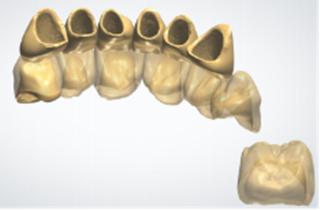

内冠回切并最终设计完成

全瓷修复后的牙齿

不到一个小时,牙龈上的黑线消失了,牙齿又恢复了往日的风采,董女士开心的笑了,她说道:“以后又可以开心的和客户交谈了,感谢熊医生,感谢麦芽口腔先进的技术,以后一定好好的护理自己的牙齿!”